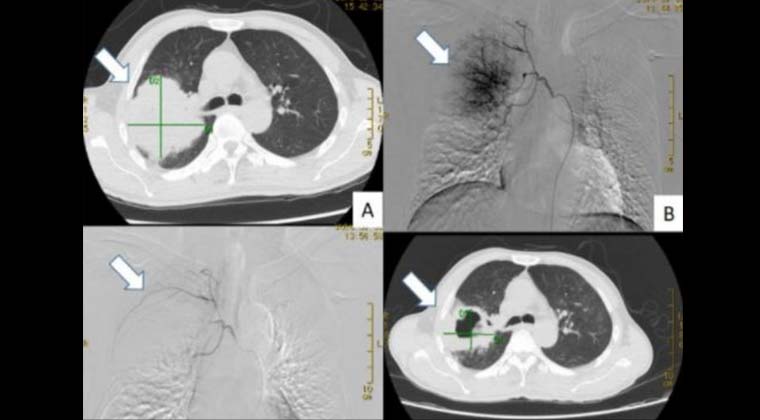

② Случай 2: Химиоэмболизация бронхиальной артерии

Пациент с раком верхней доли правого легкого, диаметр опухоли около 8 см (левый верхний снимок);

Использованы микросферы с лекарственным препаратом для химиоэмболизации бронхиальной артерии,

(правый верхний снимок) отчетливо видна сосудистая сеть опухоли,

(левый нижний снимок) после эмболизации окрашивание опухоли полностью исчезло;

Через 1 месяц после процедуры контрольные изображения показали выраженный некроз опухоли и уменьшение диаметра до примерно 4 см (правый нижний снимок).

Пациент продолжил комплексное лечение, жив более года и находится на постоянном наблюдении.